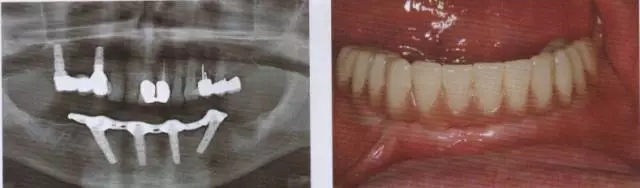

圖13 在取下上部結(jié)構(gòu)后可以看到完全無(wú)刺激反應(yīng)的軟組織

圖14 在下頜種植手術(shù)一年后可以看到種植體周?chē)撬椒€(wěn)定且拔牙窩形成進(jìn)一步的骨再生

圖15 在帶入終修復(fù)體后檢查,種植體完全無(wú)炎癥